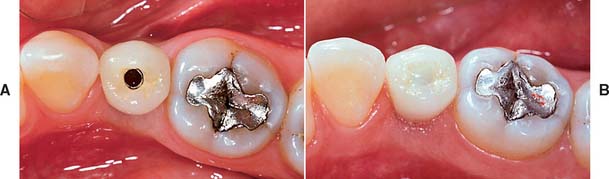

Accurately mounted diagnostic casts (see Chapter 2) are essential for treatment planning. They are used to study the remaining dentition, evaluate the residual bone, and analyze maxillomandibular relationships. They can be helpful to the surgeon for fixture placement. A diagnostic waxing is performed on the cast or on a duplicate. Proposed fixture installation sites are checked for proper alignment, direction, location, and relation to the remaining dentition. The waxing helps determine the most esthetic placement of the teeth to be restored and the potential for functional speech disturbances. After adjustments and the diagnostic waxing are completed, a resin template can be made from the cast to guide the surgeon during implant placement (Fig. 13-9). Diagnostic waxings and surgical templates are essential when implants are planned as part of a full-mouth reconstruction or when the anterior esthetic zone is restored (Fig. 13-10).

Fig. 13-9 A, Patient with bilateral missing posterior teeth planned for posterior implant-supported restorations. B, Diagnostic cast. C, Diagnostic denture tooth arrangement to simulate three-unit fixed prostheses on each side of the mandible. D, Vacuumed matrix formed over the cast with 1.5-mm (0.060-inch) thermoplastic sheet. E, The matrix is marked with the most appropriate implant locations and alignments and then removed from the cast. F, The completed surgical guide with holes drilled to guide the surgeon during implant site preparation.

Fig. 13-10 A, Diagnostic cast with missing maxillary left lateral incisor. B, The denture tooth is positioned for optimum esthetics. C, The denture tooth is trimmed from the lingual side until it is 2 mm thick. D, If the tooth is held in position with light-cured composite, a vacuum matrix can be performed directly without duplicating the cast. E, The matrix can be trimmed to the height of contour with a stiff bristle brush. F, The denture tooth can be glued back into the matrix. G and H, The surgeon can use this template to guide both horizontal and vertical positioning.